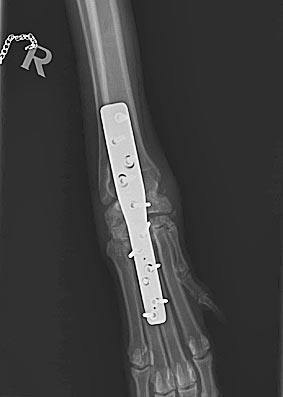

Kurz vor Weihnachten 2016 hat Carla sich beim Toben einen Bruch und kompletten Bänderriss im Karpalgelenk zugezogen.

Nachdem das Gelenk mit einer Platte und 11 Schrauben versteift wurde, mussten wir sie monatelang schonen.